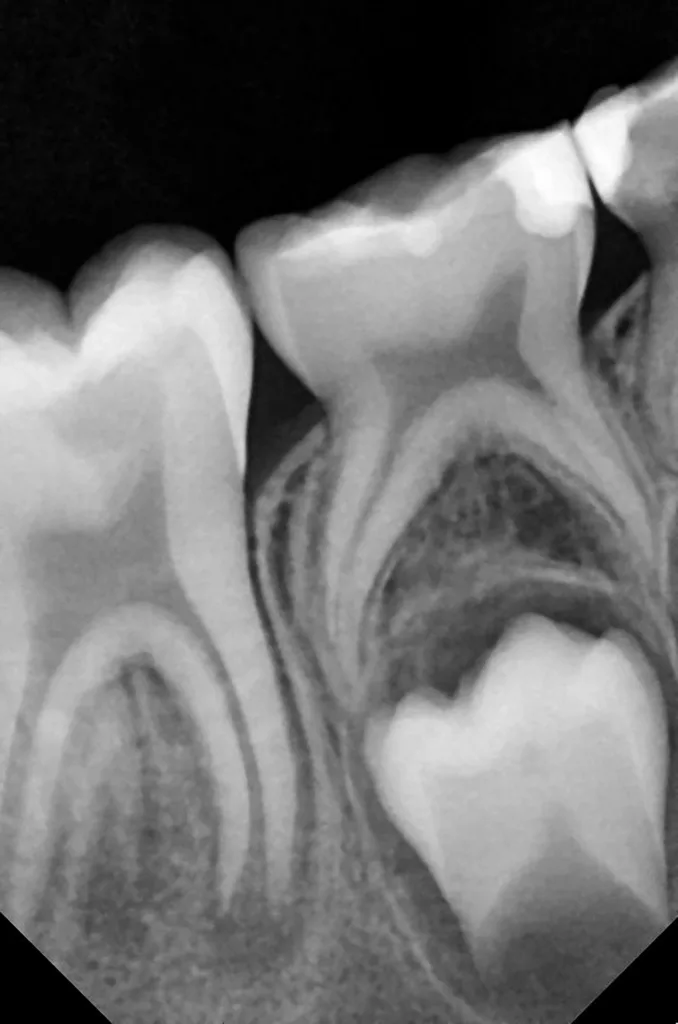

Bei routinemäßigen Röntgenkontrollen ergeben sich manchmal Zufallsbefunde unklarer Genese. So stellt sich beispielsweise bei der Betrachtung der Abbildung 1 die Frage, wie sich ein Zahnhartsubstanzdefekt so schnell entwickeln konnte. Ein weiteres Röntgenbild (Abb. 2), das vor dem Zahndurchbruch aufgenommen wurde, zeigt jedoch, dass es sich in diesem Fall nicht um Karies, sondern um die sogenannte präeruptive intrakoronale Resorption (PEIR) handelt. Für diesen Befund finden sich in der Fachliteratur auch noch andere Bezeichnungen wie „idiopathic external resorption of unerupted permanent teeth“ [1], „intra-follicular caries“ [2], „radiolucent lesions resembling caries“ [3], „occult caries“ [ 4] oder „pre-eruptive caries“ [5].

V. Slabkovskyi, O. LiutikovJahr vor dem Durchbruch des Zahnes 36.

Das fünfjährige Mädchen stellte sich 2017 zur jährlichen Routinekontrolle vor. Im Rahmen der Untersuchung wurden Röntgenaufnahmen der Milchmolaren gemacht (Abb. 2). Der klinische und radiologische Befund der vor uns früher gelegten Kompositfüllungen war gut, es wurde allerdings eine PEIR an den noch nicht durchgebrochenen ersten bleibenden Molaren festgestellt (Abb. 2). Den Eltern wurde empfohlen, sich unverzüglich bei Beginn des Durchbruchs der ersten Molaren erneut zur Behandlung vorzustellen. Ein Jahr später erschien die junge Patientin schmerzfrei zur Kontrolle. Der Zahn 36 war noch teilweise mit Gingiva bedeckt. Auf einer neuen Röntgenaufnahme (Abb. 1) wurde die PEIR-Läsion mit unveränderter Größe in pulpanahen Bereichen bestätigt (Grad 3 der Läsion nach Seow). Der Zahnschmelz sah intakt aus, es konnte kein pathologischer periapikaler Befund bei den noch nicht ausgewachsenen Zahnwurzeln festgestellt werden. Daraufhin wurden die verschiedenen Behandlungsmöglichkeiten von Fissurenversiegelung bis Vitalerhaltung der Zahnpulpa mit den Eltern des Kindes besprochen.